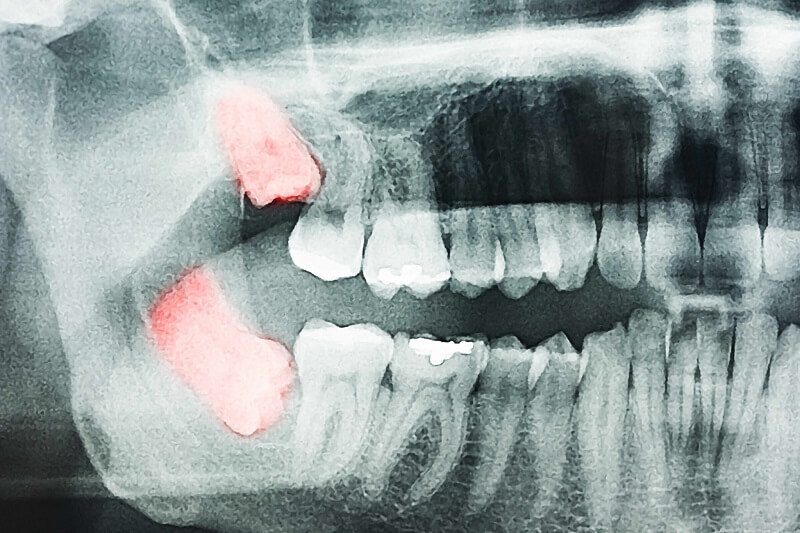

Tiêu chân răng: Các răng khôn hàm dưới nằm ngang, đâm vào chân răng bên cạnh, có thể gây tiêu chân răng kế cận nó.

U và nang xương hàm: Trong một số trường hợp, u và nang xương hàm xuất hiện ở vùng răng khôn phá hủy cấu trúc xương hàm, ảnh hưởng răng và các cấu trúc xung quanh.